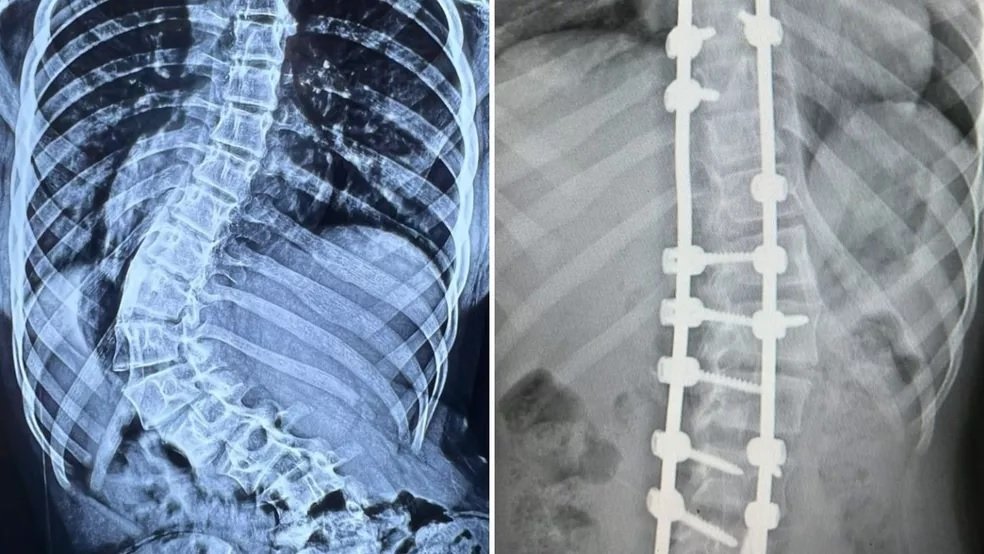

Após cirurgia, menina que tinha ‘coluna em S’ anda pela 1ª vez com postura correta: ‘Aliviada e feliz’, diz mãe

Nesta semana, ela deu os primeiros passos após o procedimento, que corrigiu uma curvatura de 100 graus em sua coluna, que já apresentava em exames um formato de “S”.

Mais de 100 graus de curvatura

Em agosto do ano passado, Agatha foi diagnosticada com Escoliose Idiopática, isto é, uma curvatura lateral da coluna.

Só que o procedimento era urgente: em apenas 5 meses, a curvatura da coluna de Agatha evoluiu de 75 para 101 graus, o que colocou sua família em estado de alerta.

Correção da curvatura

Mais de 7 meses depois do diagnóstico de Escoliose Idiopática, enfim, a família pôde respirar aliviada: isso porque a cirurgia foi realizada na última sexta-feira (11), sem maiores complicações.

Apesar da complexidade do procedimento – que levou 7 horas para ser concluído, – os pais de Agatha estão esperançosos e confiantes na plena recuperação da filha.

De acordo com o cirurgião Luciano, após a alta hospitalar, Agatha deverá comparecer a 10 consultas de fisioterapia e fazer uso de um colete até estar 100% recuperada.